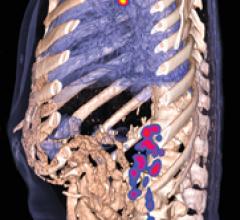

May 26, 2015Detecting metastatic disease early is key. Sand Lake Imaging, Florida, provides great value to both patients and referrers by using syngo.via's efficient AV tools. See how!

April 28, 2015The new syngo.via from Siemens Healthcare supports oncological treatment decisions across modalities, therapies and departments to enable state-of-the-art cancer care, increased competitiveness, and high referrer and patient satisfaction. syngo.via can be used as a standalone device or together with a variety of syngo.via-based software options, which are medical devices in their own right. syngo.via VB10 and the syngo.via VB10 based software options are currently under development, and not for sale in the U.S., China and other countries. Due to regulatory reasons its future availability cannot be guaranteed. Please contact your local Siemens organization for further details.